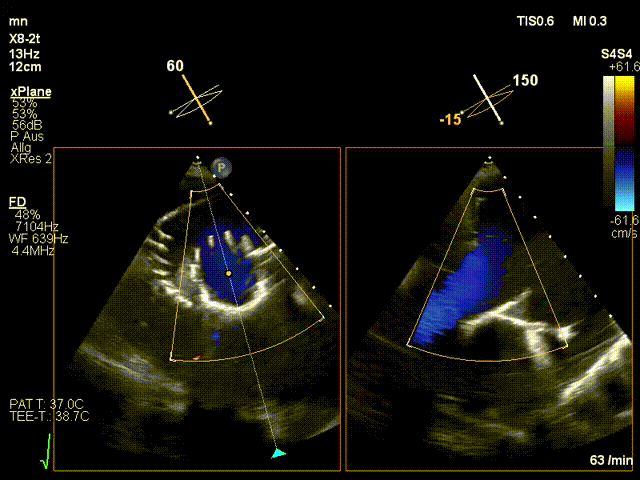

手術在全麻狀態下進行。在加拿大圣保羅醫院的Anson Cheung教授的指導參與下,術者采用經右側頸靜脈入路的方式將輸送器送入患者心臟內,在TEE及DSA引導下調整輸送器頭端角度,使得輸送器與三尖瓣瓣環平面垂直。在輸送器進入右心室后釋放室間隔錨定裝置,而后釋放瓣葉夾持件(2個耳片結構)成垂直狀態。在TEE及DSA確定夾持件固定至三尖瓣葉根部且位于右室側后釋放人工瓣心房側盤片。隨后調整瓣膜同軸性以及室間隔錨定件位置(貼合室間隔),前推藏針管并固定,進而釋放室間隔錨定裝置,并再次確認瓣膜位置、穩定性及同軸性,合攏輸送鞘后撤出輸送器,完成LuX-Valve Plus人工三尖瓣瓣膜的植入。

LuX-Valve Plus經血管三尖瓣置換系統本次“出海”圓滿完成,術后Jörg Hausleiter教授對LuX-Valve Plus經血管三尖瓣置換系統的器械性能和治療效果大為稱贊,認為LuX-Valve Plus的手術體驗非常好。術后即刻超聲顯示三尖瓣反流消失,血流動力學改善顯著,患者恢復快。Anson Cheung教授也肯定了LuX-Valve Plus術中操作的便捷性,認為LuX-Valve Plus容錯率高,對術中影像的依賴較小,后期希望可以更多的應用LuX-Valve Plus三尖瓣置換系統于臨床實踐,讓更多的三尖瓣重度反流患者盡早獲益,改善預后。